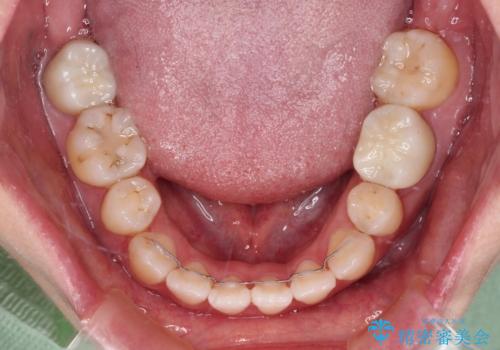

- 八重歯と前歯のデコボコ、開咬を気にして来院された患者様です。

抜歯矯正が必要であることはご自身で理解されており、目立たない装置をご希望であったので、上顎が裏側装置であるハーフリンガル装置にて治療を行うこととしました。

上顎前歯や下顎大臼歯に根管治療の必要な歯がいくつかあるため、矯正治療と並行して根管治療を行い、その後オールセラミッククラウンにて補綴治療を行うこととしました。